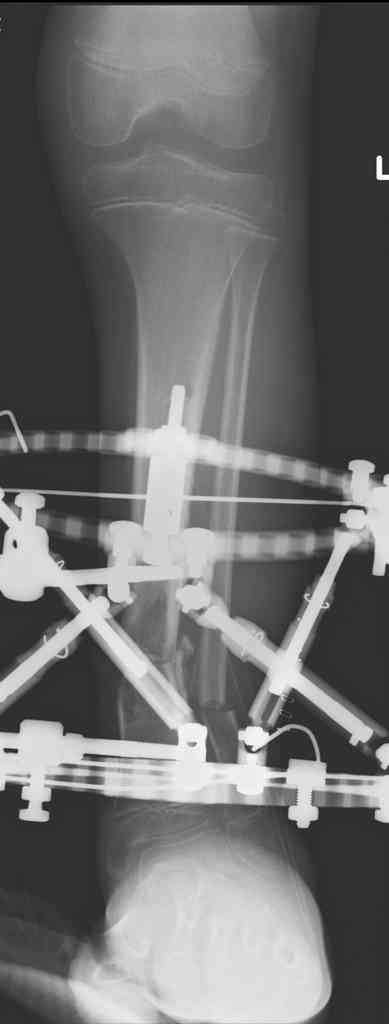

1 - рентгенограмма (прошу прощения за качество) при поступлении;

2 - внешний вид голени;

Произведено ПХО, acute shortening (5 см), фиксация стержневым аппаратом Hoffman.

3,4 - через 4 недели наложен спице-стержневой аппарат, произведена остеотомия большеберцовой кости в верхней трети, раны зажили, проводилась дистракция в аппарате.